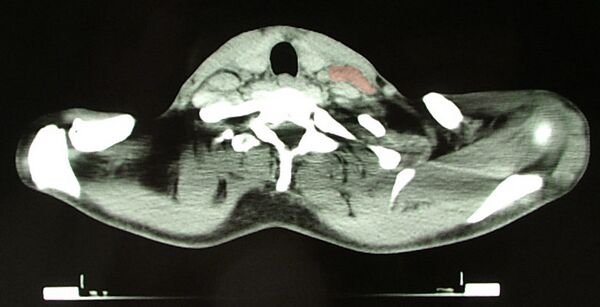

Основным критерием для постановки диагноза служит обнаружение гигантских клеток Рид — Березовского — Штернберга и/или клеток Ходжкина в биоптате, извлечённом из лимфатических узлов. Используются и современные медицинские методы: (ультразвуковое исследование органов брюшной полости, компьютерная рентгеновская или магнитно-резонансная томография органов грудной клетки). При выявлении изменений в лимфатических узлах необходима гистологическая верификация диагноза.

- Компьютерная томография, ПЭТ/КТ.